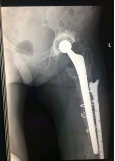

病例2 患者譚某,女性,79歲,左髖關(guān)節(jié)行置換手術(shù)14年,行翻修手術(shù)8年,兩小時(shí)前摔傷致左髖關(guān)節(jié)翻修術(shù)后假體周圍骨折,到我院住院治療,專家團(tuán)隊(duì)討論后,決定進(jìn)行二次翻修手術(shù),二次翻修相比第一次翻修,手術(shù)難度更大,面臨的困難更多,經(jīng)過精心的術(shù)前設(shè)計(jì),周密的術(shù)前準(zhǔn)備,手術(shù)過程順利,術(shù)后效果良好。

術(shù)前X線片

術(shù)后X線片